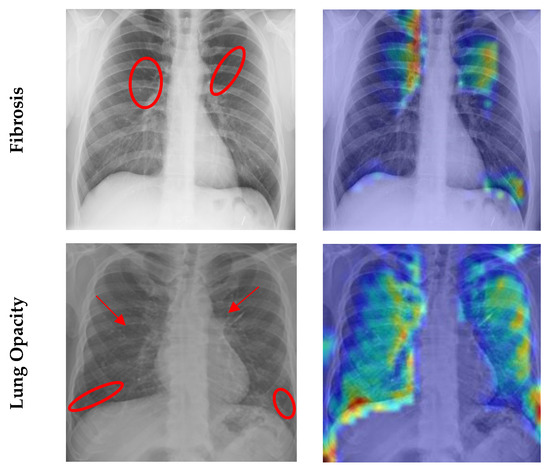

4.7. Grad CAM Visualisation